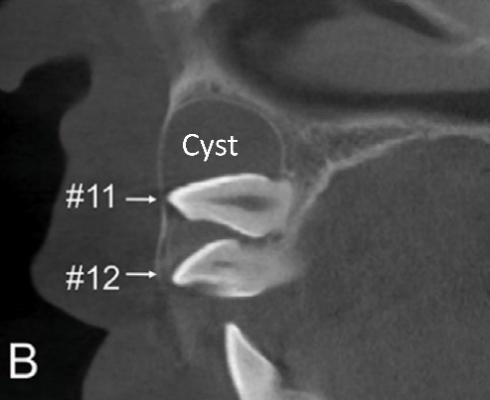

A 11-year-old girl came to our hospital complaining about “missing” front teeth. Radiographs showed that the right maxillary permanent canine, lateral and central incisors were all impacted. Particularly frustrating were the two closely stacked incisors with the roots excursing far away from the right position and embraced in a big cyst. If the incisors could not be drawn and aligned, the girl would have to face a front-teeth-missing adolescence with affected facial esthetics, oral function and self-confidence.

The orthodontic team made a delicate treatment plan after comprehensive examination and analyses. The three impacted teeth were under traction one by one, and the long-distance controlled root tipping was achieved with precise biomechanics. More importantly, a novel crimpable “gate spring”, invented by Prof. Yu Li and Prof. Zhihe Zhao, was used to boost the large-angle root torque movement with high efficiency, playing a pivotal role in perfection of this case.